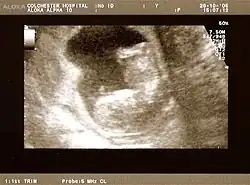

Fetus at 20 weeks

Fetal assessments

Obstetric ultrasonography is routinely used for dating the gestational age of a pregnancy from the size of the fetus, determine the number of fetuses and placentae, evaluate for an ectopic pregnancy and first trimester bleeding, the most accurate dating being in first trimester before the growth of the foetus has been significantly influenced by other factors.[22] Ultrasound is also used for detecting congenital anomalies (or other foetal anomalies) and determining the biophysical profiles (BPP), which are generally easier to detect in the second trimester when the foetal structures are larger and more developed.[23]

X-rays and computerized tomography (CT) are not used, especially in the first trimester, due to the ionizing radiation, which has teratogenic effects on the foetus.[24] No effects of magnetic resonance imaging (MRI) on the foetus have been demonstrated,[25] but this technique is too expensive for routine observation. Instead, obstetric ultrasonography is the imaging method of choice in the first trimester and throughout the pregnancy, because it emits no radiation, is portable, and allows for realtime imaging.[26]

The safety of frequent ultrasound scanning has not been confirmed. Despite this, increasing numbers of women are choosing to have additional scans for no medical purpose, such as gender scans, 3D and 4D scans.[27] A normal gestation would reveal a gestational sac, yolk sac, and fetal pole.[28]

The gestational age can be assessed by evaluating the mean gestational sac diameter (MGD) before week 6, and the crown-rump length after week 6. Multiple gestation is evaluated by the number of placentae and amniotic sacs present.[29]